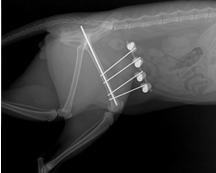

교통사고, 낙상으로 인해 발생하는 골절 정복을 골절의 유형과 환자의 상태를 고려하여 실시하고 있습니다. 고양이에서 골절이 잘 발생하는 위치는 하악골, 요/척골, 대퇴골, 사지 지골 등이 있으며, 고양이의 경우 장기간의 입원이 필요한 골절 수술 후에도 안정적인 입원 환경을 구축하여 환자의 빠른 회복을 돕고 있습니다.

• 수술 후 X-ray